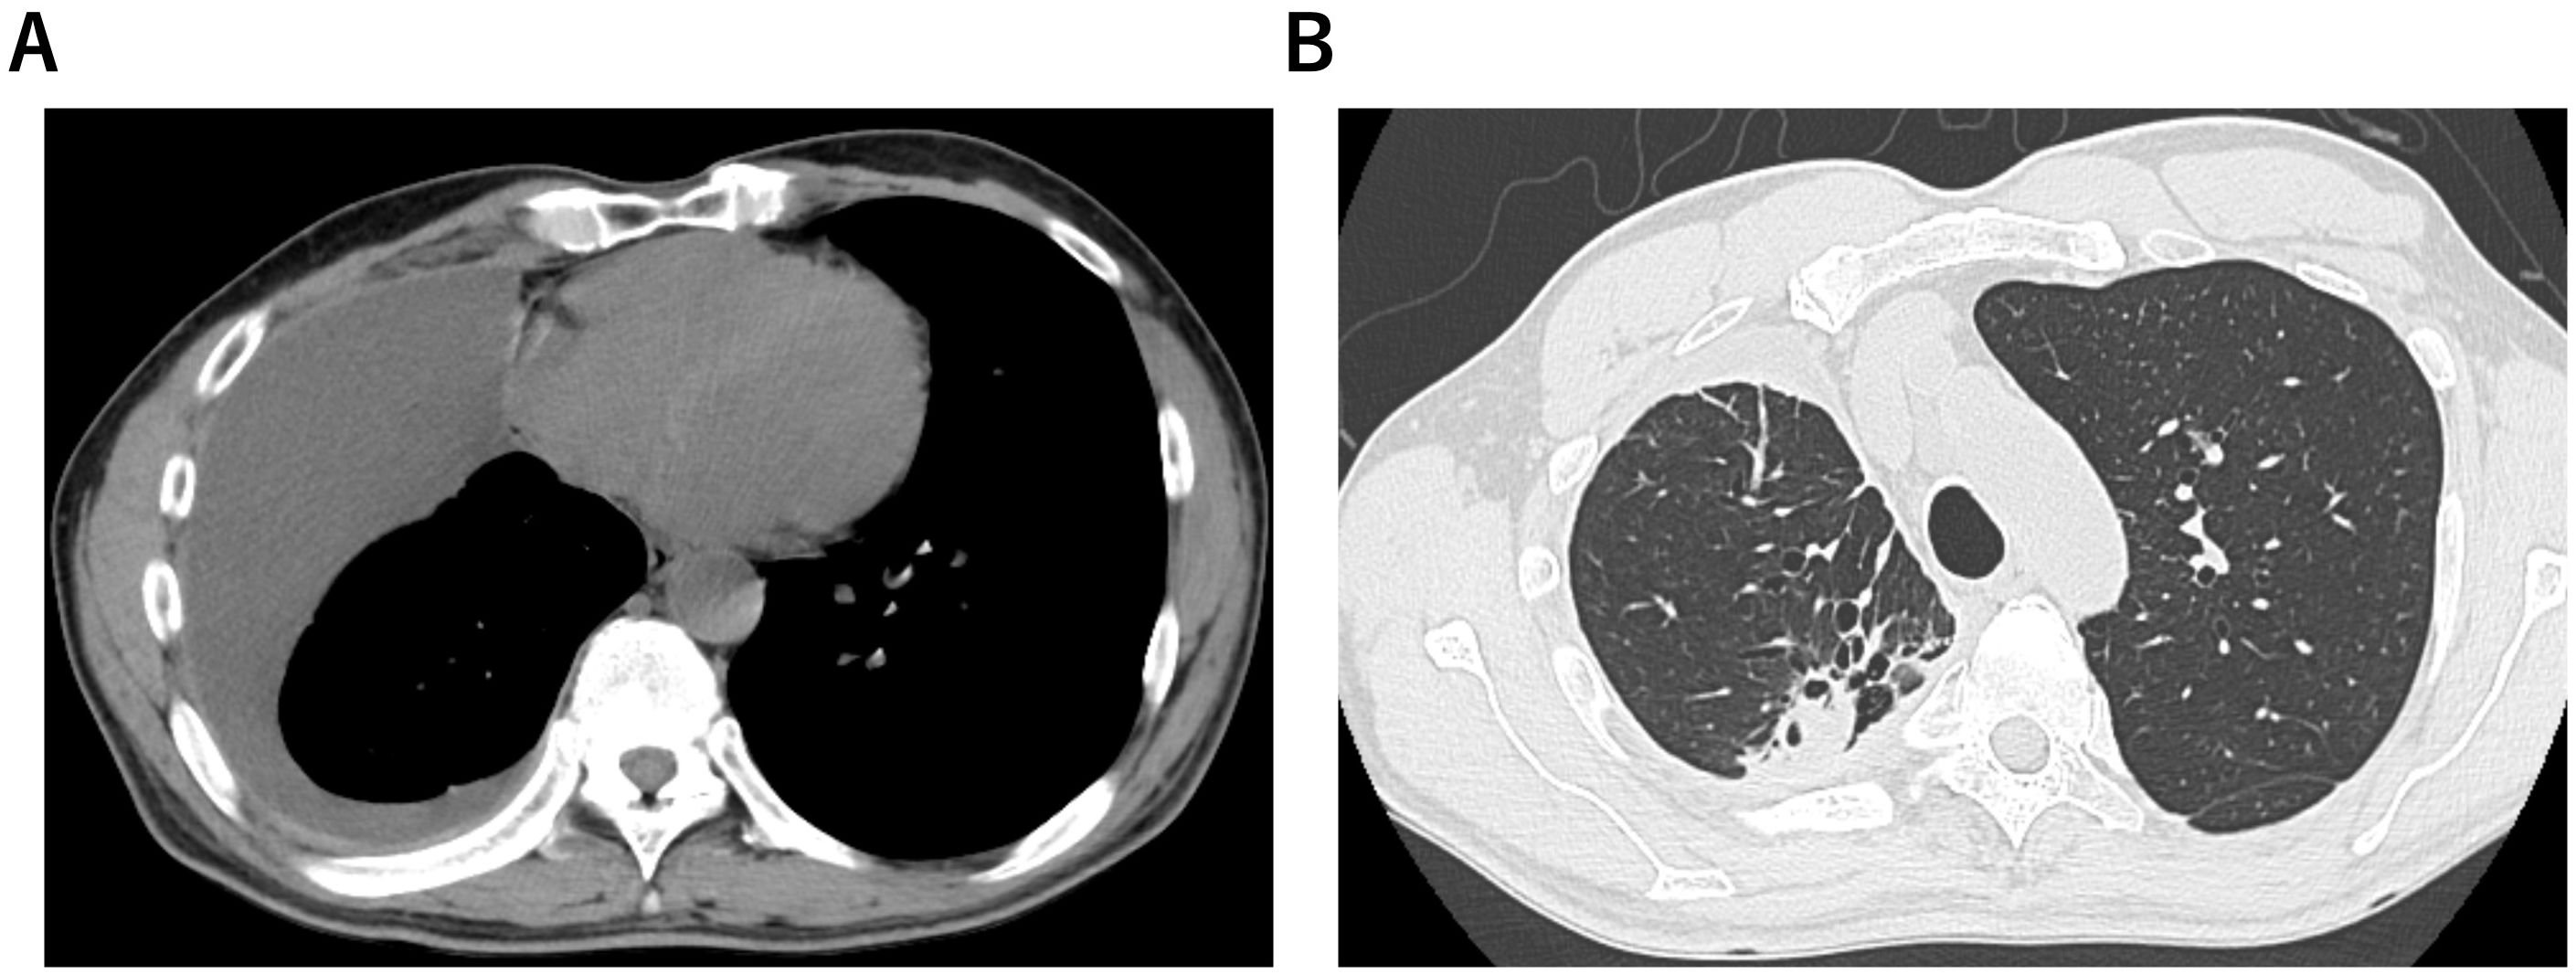

Background: Amivantamab, a bispecific antibody against epidermal growth factor receptor and mesenchymal-epithelial transition receptors, has been approved for certain types of non-small cell lung cancer; however, it is known to cause severe adverse events. The management of such adverse events is necessary for maintaining the therapeutic efficacy of amivantamab. The frequency of cardiotoxicity caused by amivantamab is low, despite its association with a high incidence of severe adverse events. Most of the adverse events are cardiovascular events caused by thrombosis. No reports of amivantamab-induced myocardial injury have been published. Case presentation: We present the first case of drug-induced myocardial injury, detected with tachycardia but not associated with any cardiovascular events, immediately after initiating amivantamab. Echocardiography revealed a decrease in left ventricular ejection fraction and global longitudinal strain, while contrast-enhanced cardiac magnetic resonance imaging showed shortened T1 values, leading to a diagnosis of amivantamab-induced myocardial injury. Furthermore, with early detection and therapeutic interventions, we were able to continue treatment with amivantamab without interruption. Conclusions: When treating patients with amivantamab, oncologists should screen for cardiac disease-related symptoms, even in the absence of elevated cardiac serum biomarkers. Furthermore, when amivantamab-induced myocardial injury is suspected, a cardiologist should be consulted promptly, as the dysfunction may be reversible.